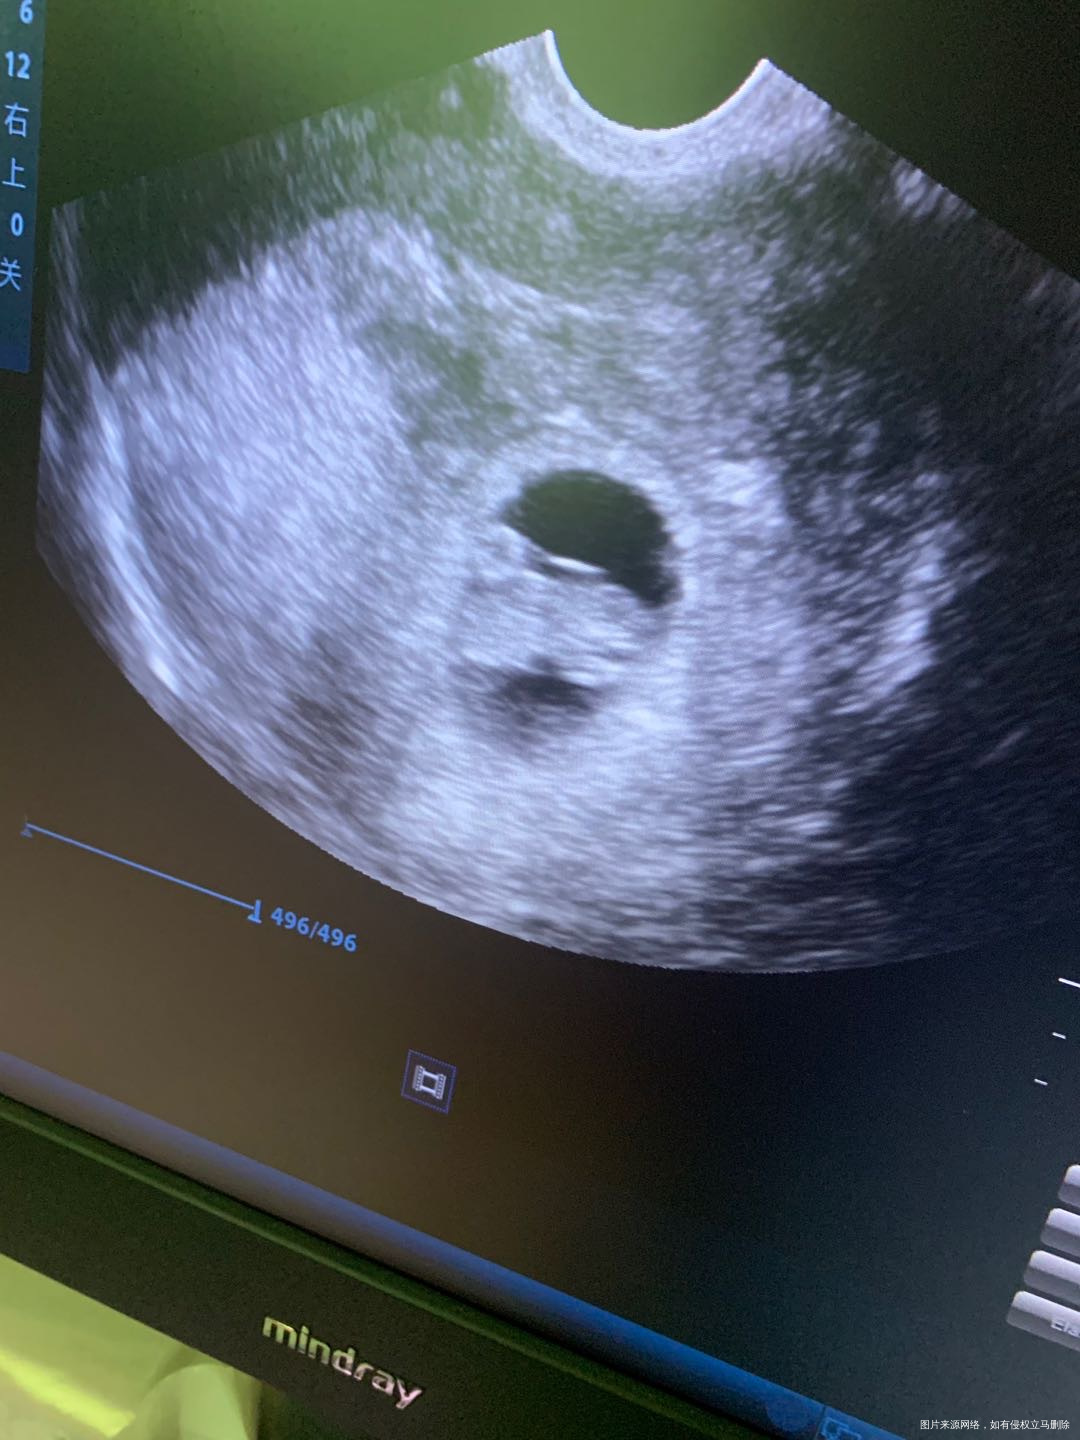

这张照片正常的吗?图品中有没有宫腔积液或者盆腔积液啥的?

这张图片没有看到明显宫腔积液和盆腔积液,看到了卵黄囊和一小胚芽,胎心要动态看,图片不是太清楚看起来难一些,恭喜宫内怀孕了,有7周左右?

A玩具Charon 回复 周加林:有八周多了 有心搏的,我就怕有积液